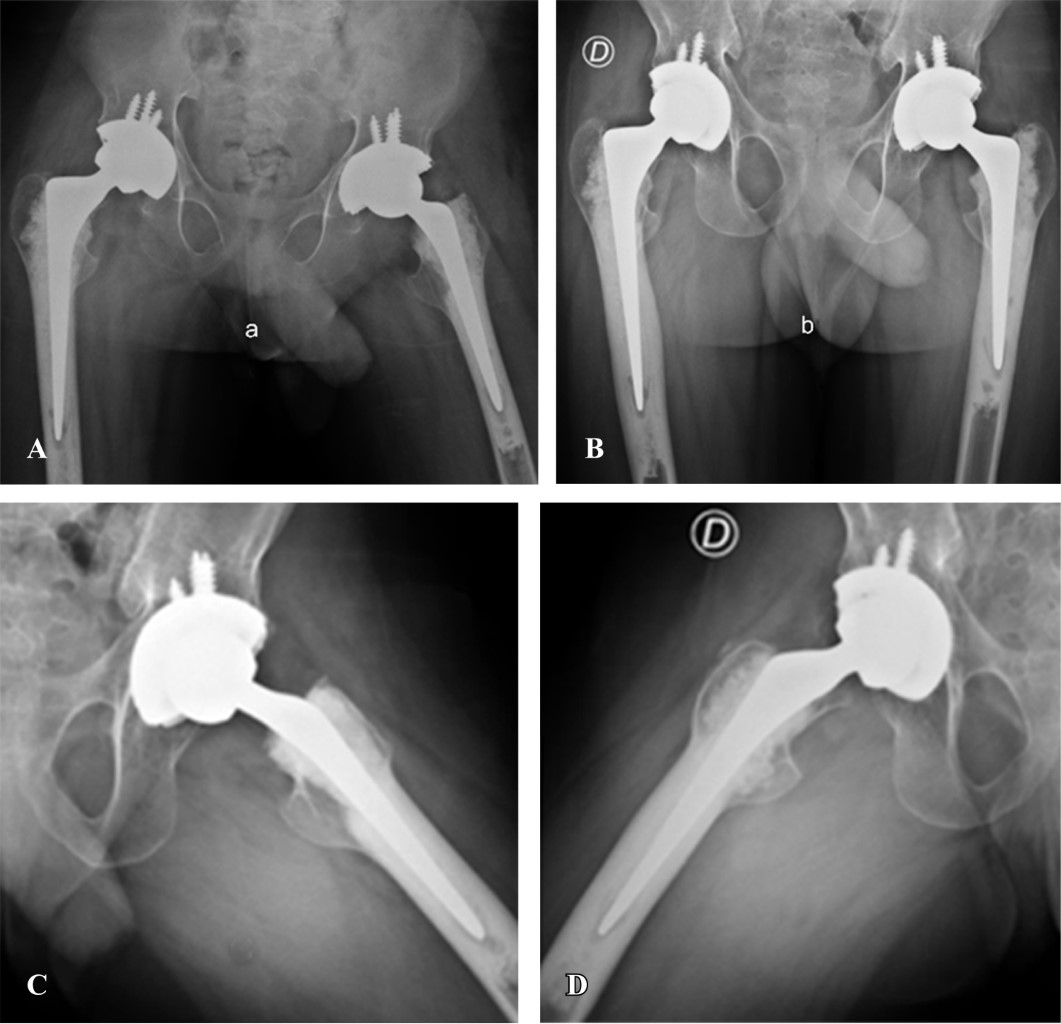

Progressive pseudorheumatoid dysplasia (PPD) is an autosomal recessive hereditary disease of very low prevalence. It is characterized by the affection of multiple joints, generating arthrosis and progressive deformities from a very young age, which significantly affect the quality of life of patients. Its diagnosis is only confirmed by genetic testing, and no specific pharmacological treatment is still available. In the case of hip involvement, one treatment option is arthroplasty. In this case report, we present a 15-year-old boy with bilateral coxarthrosis secondary to PPD who underwent bilateral total hip arthroplasty in two stages. We highlight the characteristics of this rare entity, the intraoperative findings, the functional outcomes, and the impact on quality of life.

Figure 2